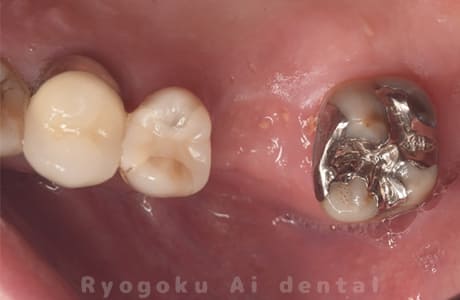

Case07

- 原因

- 右下6番歯根破折

-

- 治療内容

- インプラント治療

- 治療費用

- 約600,000円

右下の腫れが治らないとの事でご来院された患者様です。歯が割れていたため、抜歯を行い、骨に代わるお薬を入れ、インプラントを埋入致しました。経過良好で大変満足していただけました。

<リスク・副作用>

治療後、痛みや違和感、出血、腫れなどが出る事があります。喫煙者、糖尿病などの方の場合、歯が生着しない場合があります。